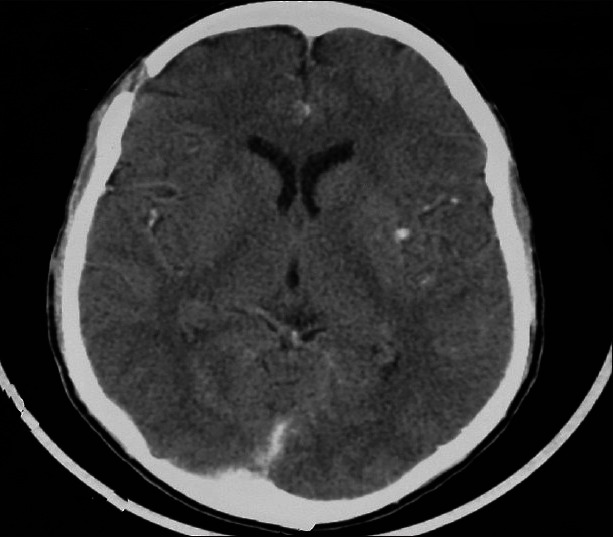

非外伤性自发性硬膜外血肿是镰状细胞病中一种罕见且常未被提及的并发症。它常与颅骨梗死有关。我们报告一位十八岁的镰状细胞性贫血的男孩,他在血管闭塞危机期间出现了持续性头痛。脑部电脑断层扫描(CT)显示右侧额叶硬膜外血肿(EDH)压迫脑部。未发现其他病因。右额叶开颅并清除血肿,患者恢复良好。本文还讨论了这种罕见疾病的可能病因。

Non traumatic spontaneous epidural Haematoma is a rare and often unmentioned complication of sickle cell disease. It is often associated with skull bone infarction. We report an eighteen year old boy with sickle cell anaemia who developed persistence headache during a vaso-occlusive crisis. Brain computed tomography (CT) revealed a right frontal epidural Haematoma (EDH) compressing on the brain. No other etiologic factor was identified. A right frontal craniotomy and evacuation of the Haematoma was performed and he made good recovery. The possible pathogeneses of this rare condition are discussed.